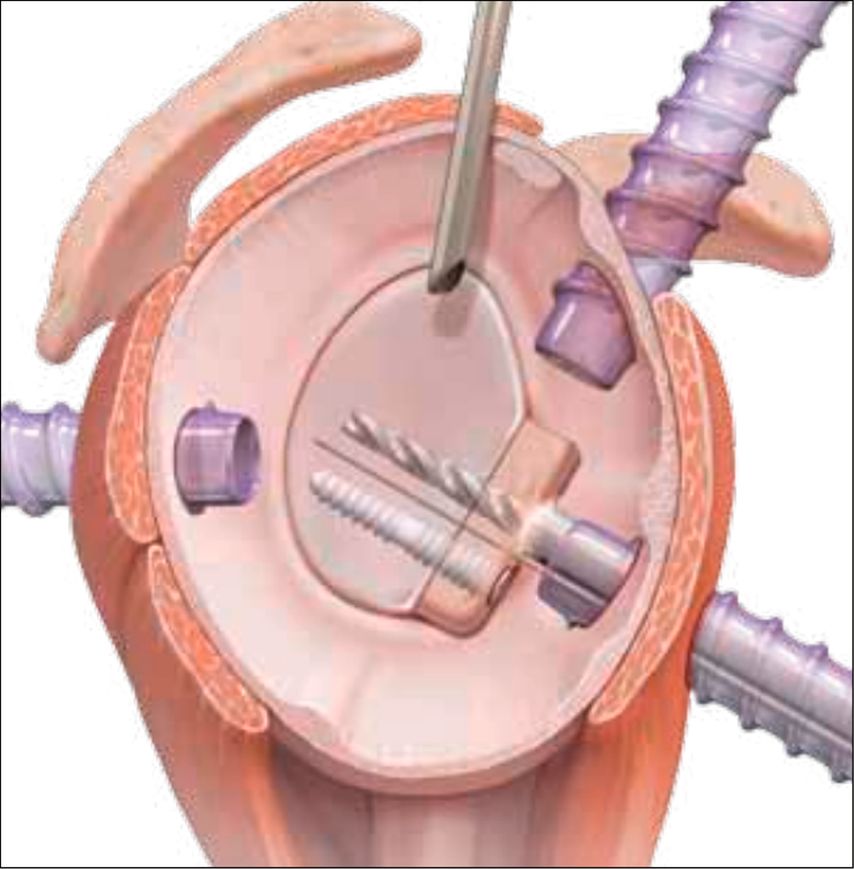

Der operative Eingriff wird in Beach-Chair- oder Seitenlagerung durchgeführt, wobei der betroffene Arm in einem Armhalter frei beweglich gelagert wird. Nach Etablierung der Standardportale – bestehend aus einem posterioren Portal zur Optik sowie anterior-inferioren und anterior-superioren Arbeitsportalen – erfolgt die arthroskopische Inspektion des Glenohumeralgelenks. Als Nächstes wird ein zusätzliches transsubskapuläres Portal (5-Uhr-Portal) angelegt (Abb.3). Die Frakturpräparation umfasst die Entfernung von Hämatom- und Interpositionsgewebe, die Mobilisation des Fragments sowie das Anfrischen der Frakturflächen zur Optimierung der knöchernen Heilung. Die Reposition erfolgt unter arthroskopischer Sicht mithilfe geeigneter Repositionsinstrumente, gegebenenfalls unterstützt durch temporäre Fixation mittels Kirschner-Draht (Abb.4).

Fixationsmethoden

Zur definitiven Fixation stehen unterschiedliche Techniken zur Verfügung. Die arthroskopisch assistierte Schraubenosteosynthese wird meistens durch das 5-Uhr-Portal durchgeführt. Kanülierte Schrauben (2,7–3,5mm) bieten, insbesondere bei größeren, kompakten Fragmenten, eine hohe Primärstabilität, ihr Einsatz ist jedoch technisch anspruchsvoll und mit dem Risiko einer intraartikulären Implantatprominenz verbunden. In den letzten Jahren sind aber Systeme mit bioresorbierbaren Implantaten hinzugekommen, die für die vordere Glenoidaugmentation entwickelt wurden (Abb. 5). Dieses System eignet sich auch perfekt für die Fixation des Glenoidfragments.